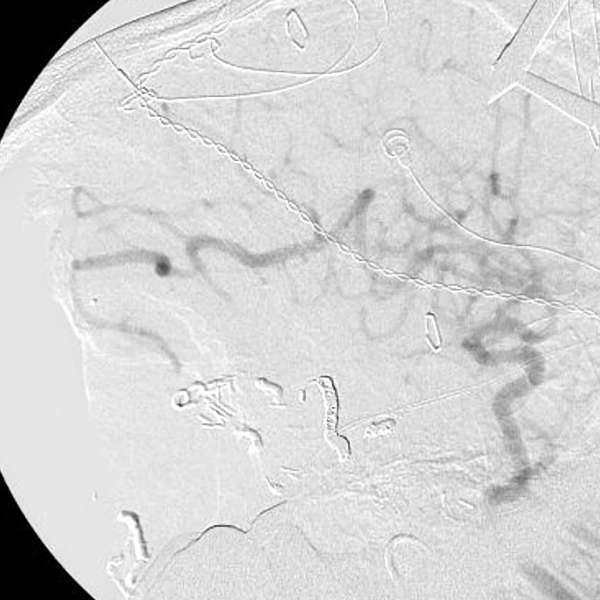

手術後

手術中